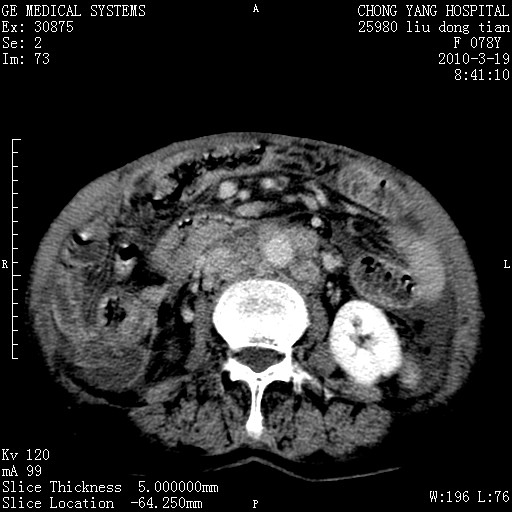

标题: CT25199:F 78Y 腹胀半年 消瘦乏力 [打印本页]

胆囊壁增厚并明显强化,胆囊癌伴多发转移瘤可能性大,淋巴瘤不除外,右肾囊肿,胸腹水.

考虑nhl,肝、脾、腹膜腔及腹膜后多发淋巴结受侵,腹水,右肾囊肿,慢性胆囊炎,右侧少量胸腔积液。

胰头有肿块形成,胰头ca伴肝脾、腹膜腹膜后转移

胆囊有软组织影有强化,支持胆囊癌,肝脾、腹膜后淋巴结转移。

nhl的淋巴结多围绕主动脉,而且主动脉会移位,所以不考虑nhl。

分开来讲:肝左叶、尾叶病灶有不均强化像肝癌;

脾脏病灶无强化,像多发囊肿或淋巴管瘤,不除外淋巴瘤(低强化);

胆囊增生性病变:胆囊癌,腺肌增生症,慢性胆囊炎;

肝门、胰腺头、腹膜后多个团块: 淋巴瘤,转移;

腔静脉肝内段细小有无布加可能?

一元论最好了 淋巴瘤所致改变; 胆囊癌转移不像,胆囊周围肝组织清晰,肝癌淋巴结转移?三元论都不止。

最后报的胰头癌多发转移,脾脏单独考虑囊肿或淋巴管瘤。